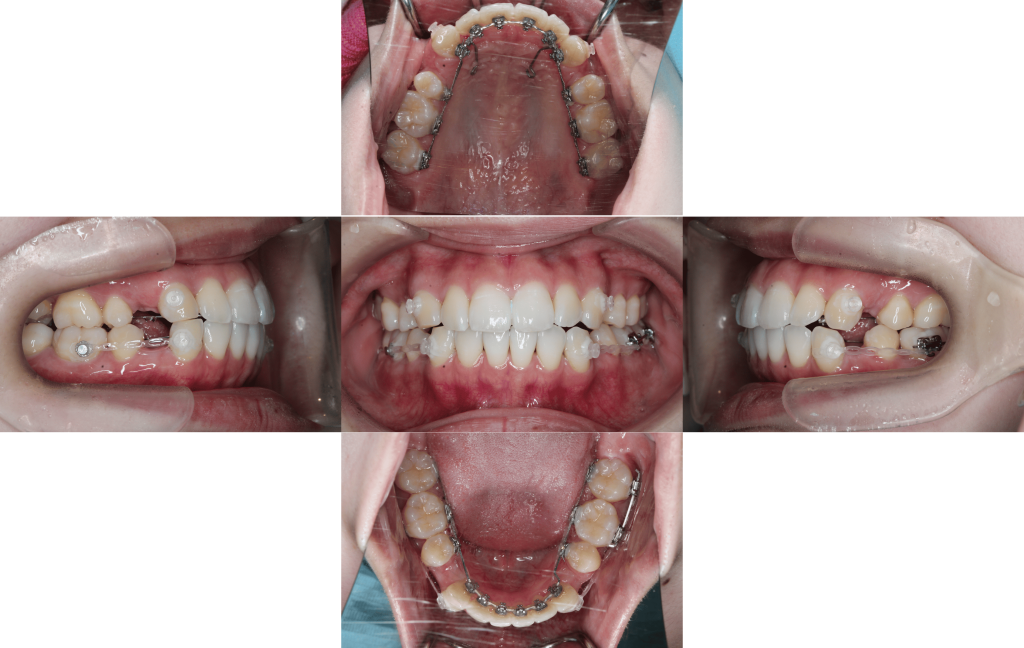

約6か月経過

約1年経過